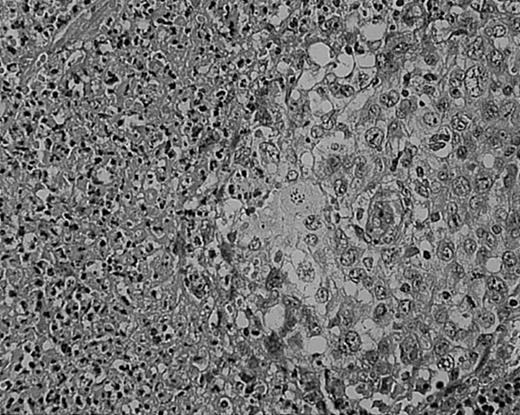

As we have previously reported, tissue eosinophilia is the strongest prognostic indicator in NS.19 Eosinophilia was not included in the BNLI criteria. We therefore propose a new grading system that includes this important risk factor and should be easier to use than the BNLI criteria. The 3 criteria of the new grading system are: eosinophilia (approximately > 5% of all cells or clusters in at least 5 high-power fields; new feature; Figure5); lymphocyte depletion (< 33% of all cells in the whole section; simplified feature of BNLI; Figure6); and atypia (> 25% of H/RS cells bizarre and highly anaplastic appearing, with pleomorphic nuclear features, hyperchromatism, and highly irregular nuclear outlines; simplified feature of BNLI; Figure 7). Cases showing none of these factors are called NS-low risk (NS-LR) and each case showing one or more of the factors is called NS-high risk (NS-HR).

Cellular atypia (left-side confluent necrosis) in NS HD.

This example shows more than 25% of H/RS cells presenting with bizarre and anaplastic appearances. Stained with H&E. Original magnification, × 400.